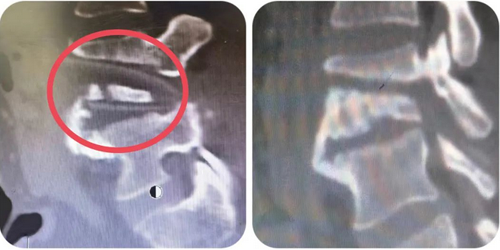

几次调整角度和透视后,第四腰椎椎体和其中镶嵌的木条也出现在了视野中,下面要面对的,便是此次手术最大的难点:如何在取出木条的同时,不损伤覆盖在椎体和木条表面的下腔静脉。

袁强不再犹豫,果断地开始分离木条周围的组织和脓苔。半小时后,凭借丰富的临床经验和高超的手术技巧,袁强在没有损伤血管的情况下,顺利取出已经断裂成几块的暗红色木条。随着腰部切口的最后一针缝合,一台3小时的高难度腰椎异物取出手术正式宣布结束。

左图标红处为木条位置,右图为术后取出影像